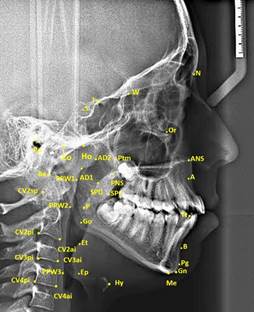

In study, 35 cephalometric points (Figure 1), 8 cephalometric planes, and 30 cephalometric measurements (Figure 2) were used. In the cephalometric analysis; 5 craniofacial, 8 nasopharyngeal, 7 oropharyngeal, 2 hypopharyngeal (Figure 3), 9 hyoid measurements (Figure 4) and 4 area measurements (Figure 5) were used.

Figure 1 Cephalometric landmarks used in study. (S: It is the geometric center point of Sella tursica; N: It is the most advanced point in the middle oxal plane, where the nasofrontal suture intersects the sagittal plane, and the deepest point of the recess in that area; Ptm: It is the lowest point of the fissure formed by the retromolar tubercle of maxillary and the pterygoid part of the sphenoid bone; PNS: It is the most posterior and end point of the hard palate in the sagittal plane; A: It is the deepest point of concave located between the anterior nasal spina and prosthion; Pg: It is the most advanced point of the mandibular symphysis in the sagittal plane; Ba: The junction between the base of the cranium and the outer edge of the clivus cranium and the endocranium edge; Hy: Hyoid is the top and anterior point of the bone corpus; P: It is the extreme point of the soft palate; Ep: The Epiglottis base is also the most posteroinferior point in the tongue base; Et: It is the end point of the epiglottis; Ho: It is the point at the intersection between the perpendicular line drawn from PNS to the Sella-Basion and the cranial base; AD1: It is the point where the line connecting the PNS and the Basion intersect the posterior of the nasopharyngeal wall; AD2: It is the point at the intersection of the line drawn from the PNS to the midpoint of the line connecting the Sella-Basion and the posterior of the nasopharyngeal wall.)